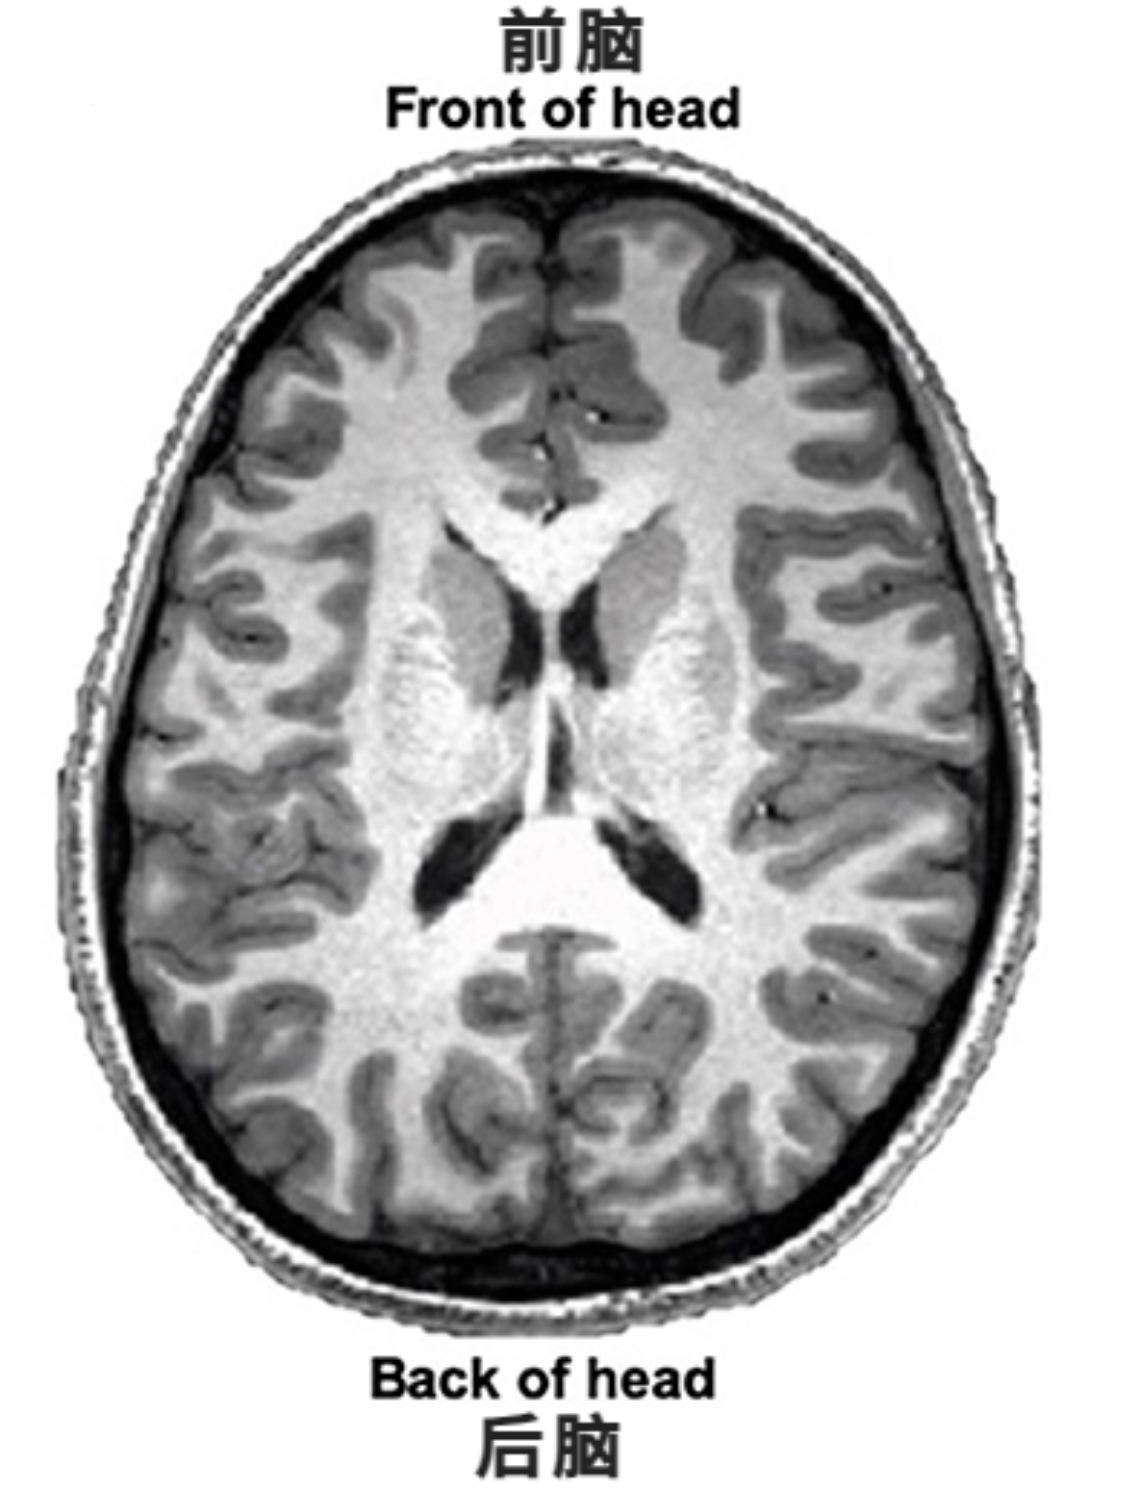

研究人员借助磁共振成像技术给一位青少年的大脑拍照,通过磁共振成像展示了人类青春期大脑结构与功能的发展变化。

▲磁共振成像设备和大脑成分结构图

▲利用磁共振成像技术获得的一张人脑图,围绕白色区域的灰色部分是大脑皮层的灰质, 白色区域则是白质。

大脑的组织结构部分主要由灰质和白质两种成分组成。

灰质由神经元细胞的胞体组成,分布在大脑皮层和大脑深处。灰质包含大部分神经元细胞体,构成了与运动控制、感知觉、做决策以及自我控制相关的脑区。

在青春期,灰质体积会随年龄增长逐渐减少约1.5%。灰质的减少被认为与脑细胞连接的微调有关,也与大脑中白质的增加有关。

白质位于大脑皮层之下,由神经元的轴突组成。轴突通过信号传递,负责将不同脑区连接起来。

在青春期早期,白质逐渐增加,但到十多岁时,增长趋势趋于稳定。白质的增加被认为与脑细胞之间信号传递的速度增强有关。